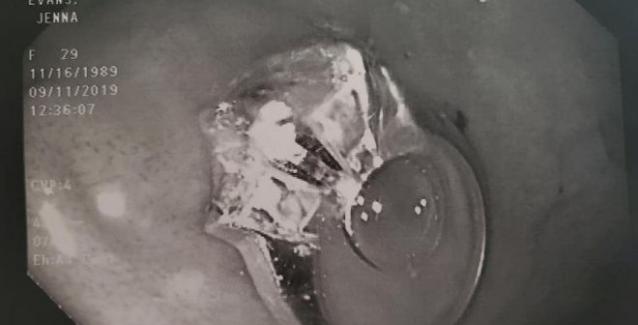

Η ακτινογραφία έδειξε ότι όντως μέσα στο στομάχι της υπήρχε το δαχτυλίδι 2.4 καρατίων και οι γιατροί τη συμβούλεψαν να υποβληθεί σε επέμβαση για να το αφαιρέσουν. Όπως η ίδια εξήγησε, της ζητήθηκε προηγουμένως να υπογράψει τα σχετικά έγγραφα σε περίπτωση που πέθαινε.